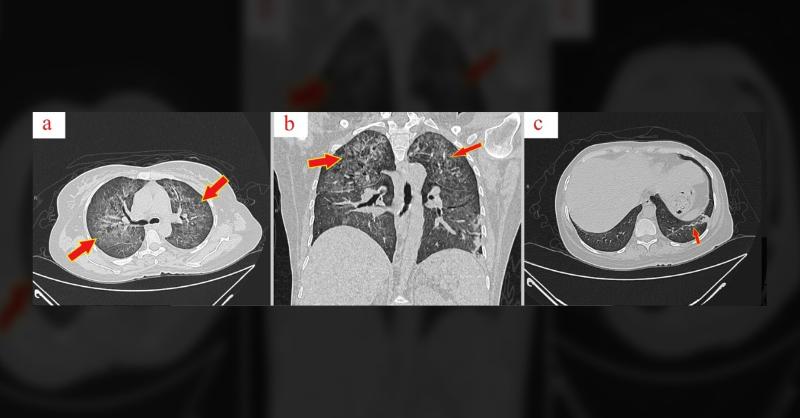

A 39-year-old woman was unexpectedly diagnosed with a medical condition, marked by symptoms such as epistaxis, heavy menstrual bleeding, and skin bleeding spots. The condition came to light incidentally during a routine complete blood count (CBC) conducted before labor, revealing a platelet count of 48,000 × 10^9/L. Despite an array of treatments,

Diagnosis of a Rare Platelet Disorder in a 39-Year-Old Woman